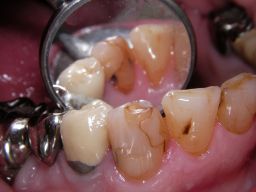

![]() | Der Eckzahn (Zahn 43) in der Mitte des Bildes zeigt an mehreren Stellen am Füllungsrand schwarze Karies, wie man hier aus verschiedenen Perspektiven sieht. Der Zahn rechts daneben auf dem Foto (Zahn 42) zeigt eine schwarze Randverfärbung einer älteren Kunststofffüllung. |